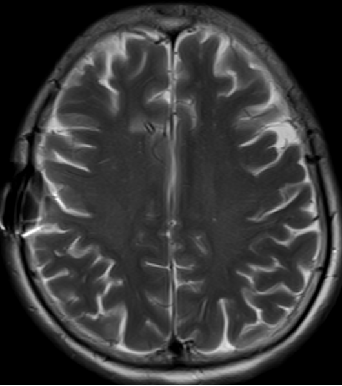

2013-8-2 MRI

2013-8-2 CT

腰穿脑压240